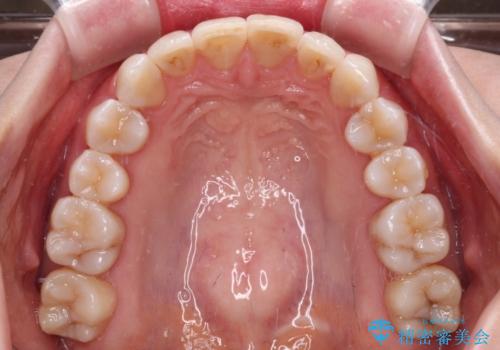

前歯の突出感とデコボコをインビザライン矯正で改善

- 上下前歯の突出感とデコボコを気にして来院された患者様です。

インビザラインによる上下歯列の側方拡大と後方移動、IPR(歯と歯の間を削る)にるスペースの獲得により歯列を整えることとしました。